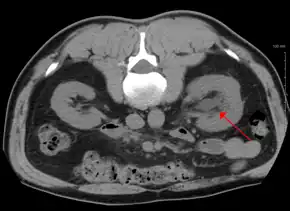

CT scan of bilateral hydronephrosis due to a bladder cancer -

Stone causing hydronephrosis[13]